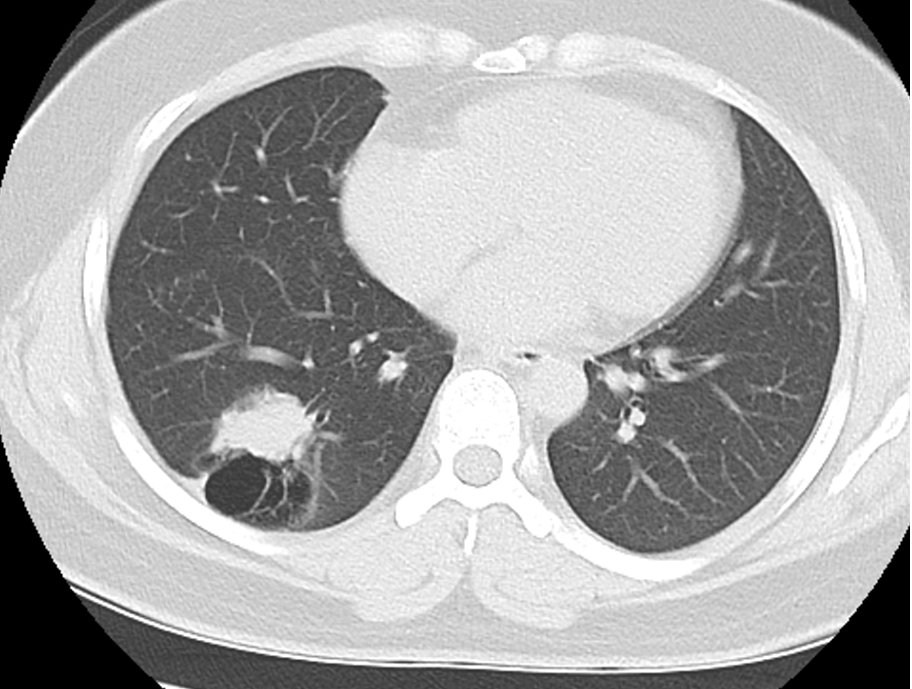

图2:术前胸部CT肺窗

上周,我收治了一位42岁男性患者,因体检发现左下肺结节4月余入院。4个月前行胸部CT检查发现“左下肺结节,大小约17mm x15mm,边缘毛糙,见分叶征、毛刺征及胸膜凹陷征,考虑肺癌,建议手术治疗。因个人原因,推迟手术。本次复诊,行胸部CT示左下肺结节有增大,大小约19*16mm,有恶性肿瘤征象,根据AJCC第八版肺癌TNM分期,目前临床诊断考虑左肺下叶肺癌 cT1bN0M0 IA2期,根据NCCN2020肺癌指南,建议行肺癌根治术。